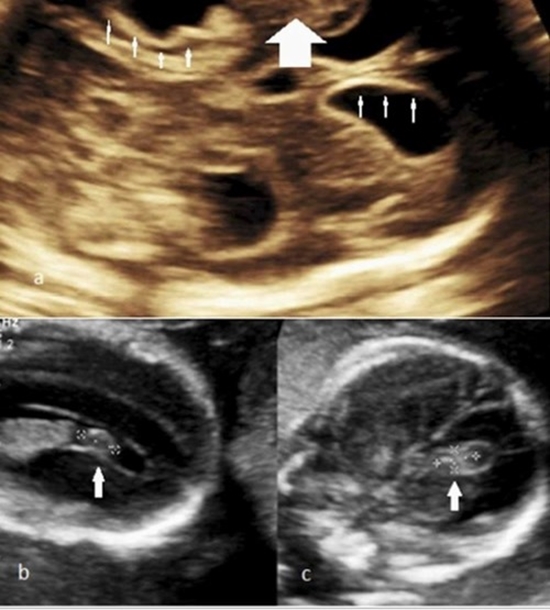

Early detection of fetal intracranial hemorrhage and infarct during pregnancy is crucial for preventing lethal and debilitating complications in neonatal life. Every radiologist must be aware of the imaging features of these conditions to refer patients to specialists. Sonographic and MRI features of fetal intracranial hemorrhage and infarct have been discussed in many previous articles. The aim of this article is to organize and categorize these findings into a practical guideline for improved application in diagnosing these diseases. The use of MRI sequences, such as DWI and multiplanar EPI should be developed for suspected prenatal infarct and intracranial hemorrhage and can serve as additional tools for early detection. In this review article, we first explain possible etiologic factors contributing to the development of fetal IVH and infarct. Then we discuss the different imaging features of these disorders on sonography and MRI separately, as well as their differential diagnosis. Finally, the mortality and morbidity associated with these two concerning fetal abnormalities will be addressed.